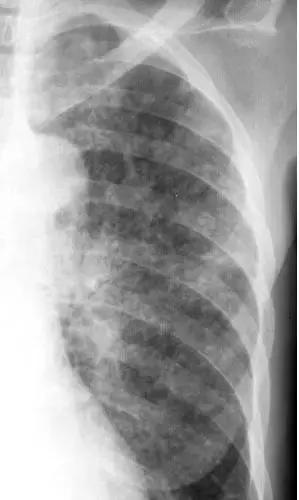

胸腔积液胸片表现图片

胸腔积液胸片表现图片,胸腔积液胸片典型图片

左边的图是典型的胸腔积液,右边的图就不典型了,这个时候就要多一个

胸腔积液胸片典型图片